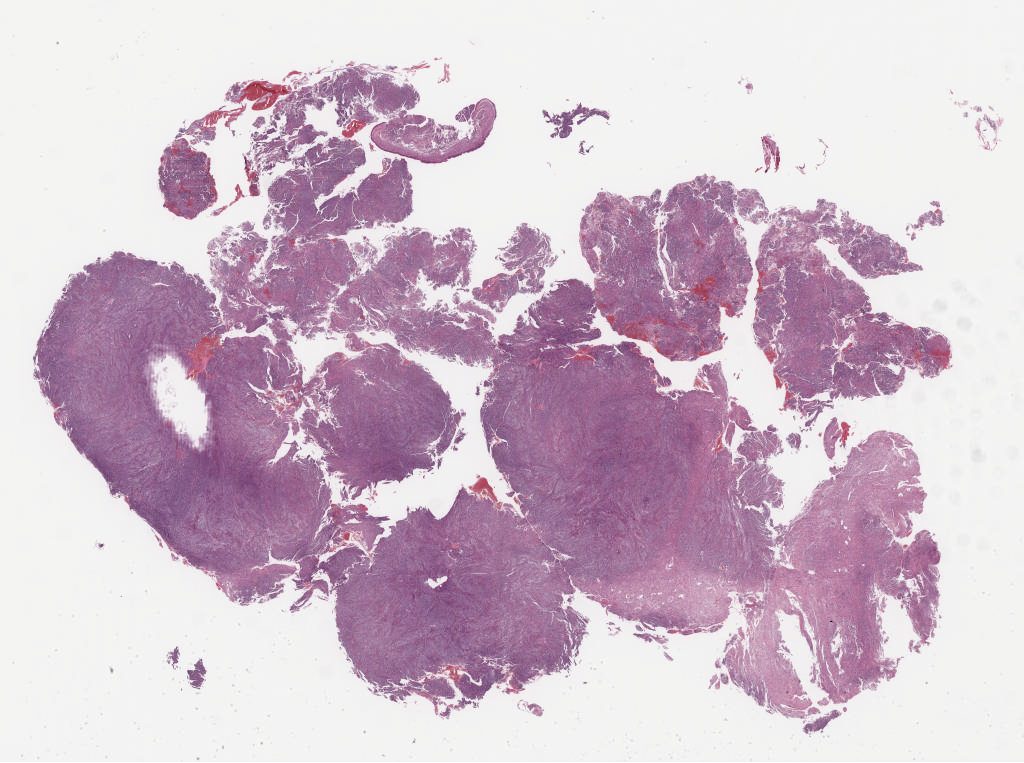

Case07.svs

57768

x

46109

@

20X